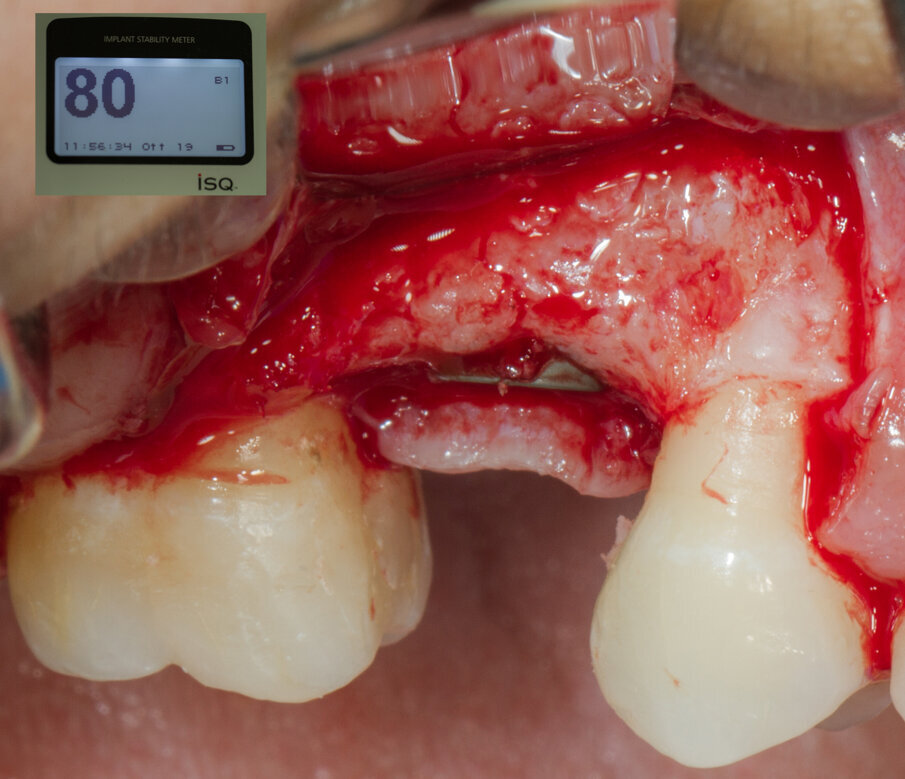

Viene inserito nel centro della cresta neoformata un impianto osteointegrato Neoss Tapered 4.0 x 13 mm con torque di inserimento di 60 Ncm e ISQ 80 (Figg. 22-24). La rigenerazione ossea crestale permette di inserire l’impianto in una posizione protesicamente guidata e con 2 mm di tessuto osseo vestibolare; questa situazione migliora la prevedibilità della riabilitazione implanto-protesica29-33. Dopo 2 mesi di provvisorizzazione si cementa il manufatto protesico definitivo (Figg. 25-28). Il controllo clinico e radiologico a 6 anni (Figg. 29, 30) mostra la stabilità dei tessuti molli e dell’osso perimplantare. Il confronto tra baseline e 6 anni dalla riabilitazione protesica evidenzia la stabilità nel tempo della rigenerazione volumetrica crestale (Fig. 31).

Fig. 22 - Impianto Neoss inserito al centro della cresta ossea.

Fig. 23 - ISQ di inserimento dell’impianto - 80.